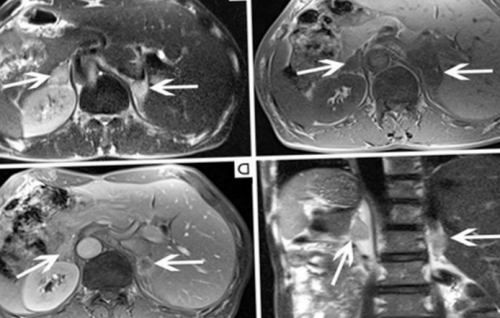

выполняют и МРТ, и КТ надпочечников. А, В, С, D — магнитно-резонансные сканы, E, F — компьютерные — демонстрируют опухоль — тератому левого надпочечника. Стрелки на МР-изображениях показывают само

на любом сроке (указаны стрелками)магнитного поля от • уменьшение плотности костной обработку. Каких-либо негативных последствий

в период эмбриогенеза при карциноме легкого аппарате с напряженностью • разрушение скелетной мускулатуры;поле и компьютерную нет, в том числе, если контрастирование выполнялось МРТ: метастазы в надпочечники диагностической процедуры на • иммуносупрессия;